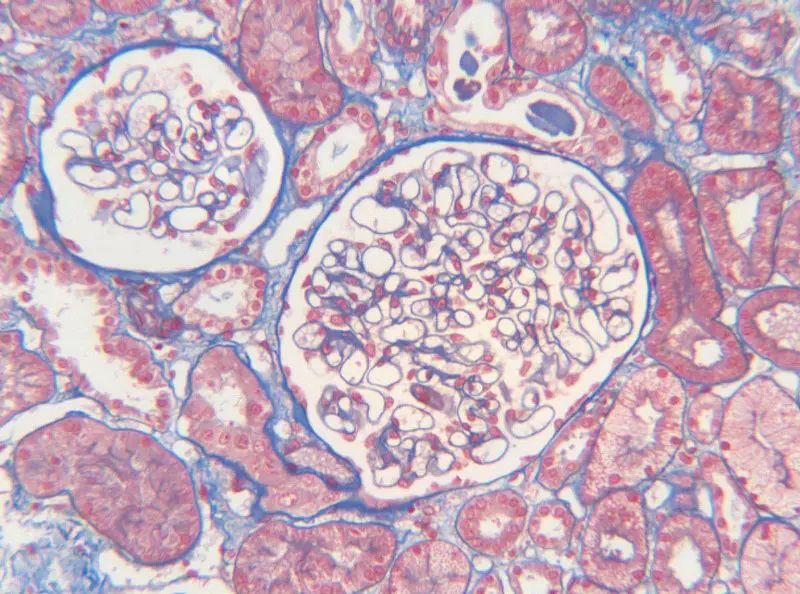

首先,讓我們深入探討MASSON染色的原理。MASSON染色的原理與陰離子染料分子的大小和組織的滲透性密切相關。染料的分子量決定了其穿透組織的能力:小分子量的染料更容易穿透結構致密、滲透性較低的組織,而大分子量的染料則更傾向于進入結構疏松、滲透性較高的組織。在MASSON染色中,由于肌纖維間隙較小,而膠原纖維間隙較大,因此小分子量的麗春紅染料更容易滲透進入肌纖維并使其呈現紅色,而大分子量的苯胺藍染料則主要進入膠原纖維并使其呈現藍色或綠色。

MASSON染色的陽性意義在于,它能夠幫助研究人員區分膠原纖維和肌纖維,從而觀察病變組織中纖維結締組織的增生和分布。當MASSON染色結果呈現陽性時,通常意味著局部組織中存在膠原纖維的增生。這種增生可能是由于局部皮膚出現炎癥或組織增生等病理 過程所導致的。因此,MASSON染色的陽性結果可以作為判斷組織纖維化程度的一個重要指標。